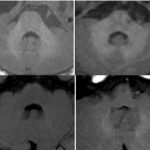

Copper-containing contraceptives are MR-friendly

This paper confirms that women with such contraceptives can safely enter MR, and that the image quality is not altered. With CT, some artefacts may appear. Article: Risk assessment of copper-containing contraceptives: the impact for women with implanted intrauterine...